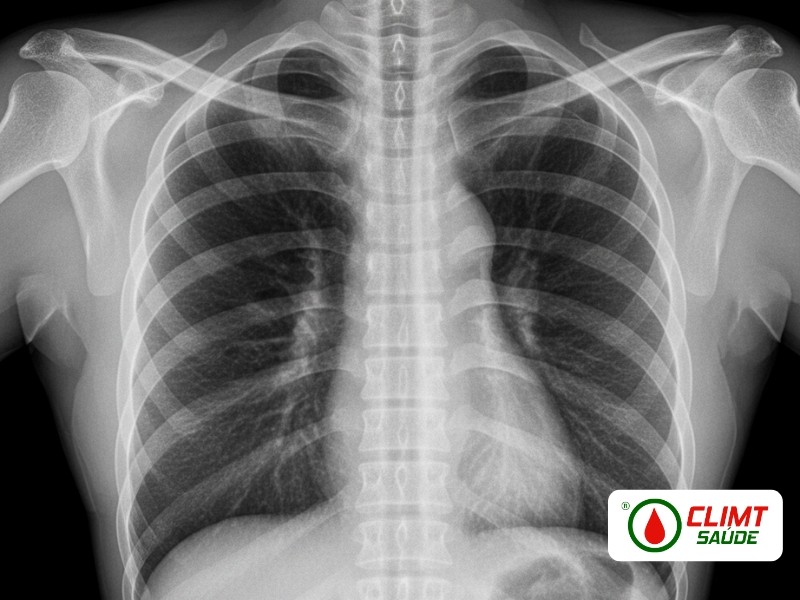

Raio X de Tórax Padrão OIT em Goiânia

Diagnóstico e monitoramento de pneumoconioses — radiologistas certificados OIT — referência desde 1995 Desde março de 1995, a CLIMT realiza o Raio X de Tórax Padrão OIT em Goiânia, referência no diagnóstico e acompanhamento de pneumoconioses e doenças pulmonares ocupacionais conforme os protocolos da Organização Internacional do Trabalho (OIT). Atendemos empresas e trabalhadores de setores expostos a poeiras minerais, sílica, amianto, carvão e outros agentes inalatórios, com laudos radiológicos padronizados, precisos e reconhecidos por órgãos públicos e fiscalizadores.

O exame segue rigorosamente os critérios técnicos estabelecidos pela Organização Internacional do Trabalho para diagnóstico padronizado de pneumoconioses.

Análise das radiografias segundo as categorias da OIT, avaliando pequenas opacidades (profusão, tamanho, forma), grandes opacidades e alterações pleurais. Interpretação exclusivamente por radiologistas certificados no sistema OIT.